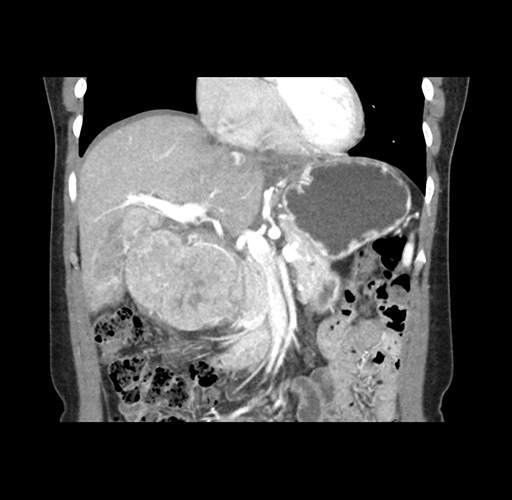

Imaging Analysis

Look through the patient's CT scan to identify any areas of concern for the necessary procedure.

Based on your CT findings, which issue(s) would give reason for "planned slowing down moment(s)" in this case?